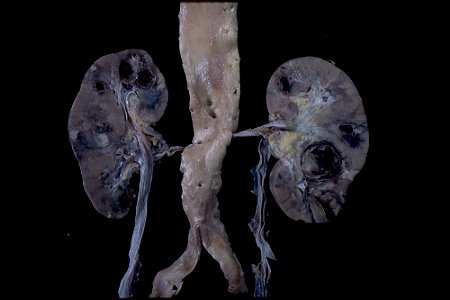

| Renal involvement by polyarteritis nodosa. Note dark thrombosed pseudoaneurysms and pale peripheral infarcts. |

![]() |

Gross changes of medium-sized vessel vasculitis

This is a similar presentation to what was seen and illustrated by Kussmaul and Maier. In this photograph, you can see that these kidneys have large aneurysms filled with clotted blood. These are really not true aneurysms; they are pseudo- aneurysms because actually the inflammatory process has eroded through the vessel wall and into the adjacent parenchyma. So it's not just a dilation of a vessel--it's an erosion through a vessel by this necrotizing process. Of course, this process can occlude the arterial arteries that are involved. You can see in the periphery here a number of infarcts, which is a complication of arteritis affecting the larger vessels in the kidney. In fact, there was rupture of one of the aneurysms. This patient actually died from massive hemorrhage into the retroperitoneal and peritoneal cavities. In this patient you can also see the typical nodular inflammatory lesion of polyarteritis nodosa as it's called today.